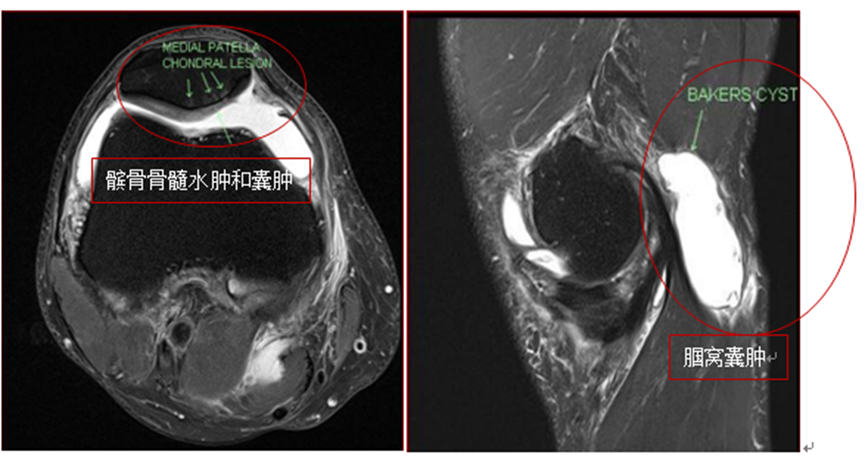

2018年10月的复查MRI显示半月板撕裂、进行中的髌骨骨髓水肿(BME)和软骨下囊肿(SBCs)以及进一步扩大腘窝囊肿的进展(如图1a和1b)。骨科医生建议采用关节镜下半月板切除术、清创术和未来的膝关节置换术进行手术干预。

图1a:间充质干细胞治疗前T2 MRI显示髌骨骨髓水肿和囊肿;1b:腘窝囊肿

图片来源:【1】